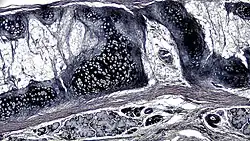

![]() A cross section of mammalian elastic cartilage | |

Elastic cartilage is histologically similar to hyaline cartilage but contains many yellow elastic fibers lying in a solid matrix. These fibers form bundles that appear dark under a microscope. The elastic fibers require special staining since when it is stained using haematoxylin and eosin (H&E) stain it appears the same as hyaline cartilage.[3] Verhoeff van Geison stains are used (giving the elastic fibers a black color), but aldehyde fuchsin stains, Weigert's elastic stains, and orcein stains also work.[3] These fibers give elastic cartilage great flexibility so that it is able to withstand repeated bending. Similarly to hyaline one or multiple chondrocytes lie between the spaces (or lacunea) in the fibres.[2] the chondrocytes only make up 2% of the tissue's volume.[2] chondrocytes and the extracellular matrix are contained in an outerlayer named the perichondrium[2] (which is a layer of dense irregular connective tissue that surrounds cartilage which is independent of the joint).[3] It is found in the epiglottis (part of the larynx), the pinnae (the external ear flaps of many mammals). Elastin fibers stain dark purple/black with Verhoeff's stain.